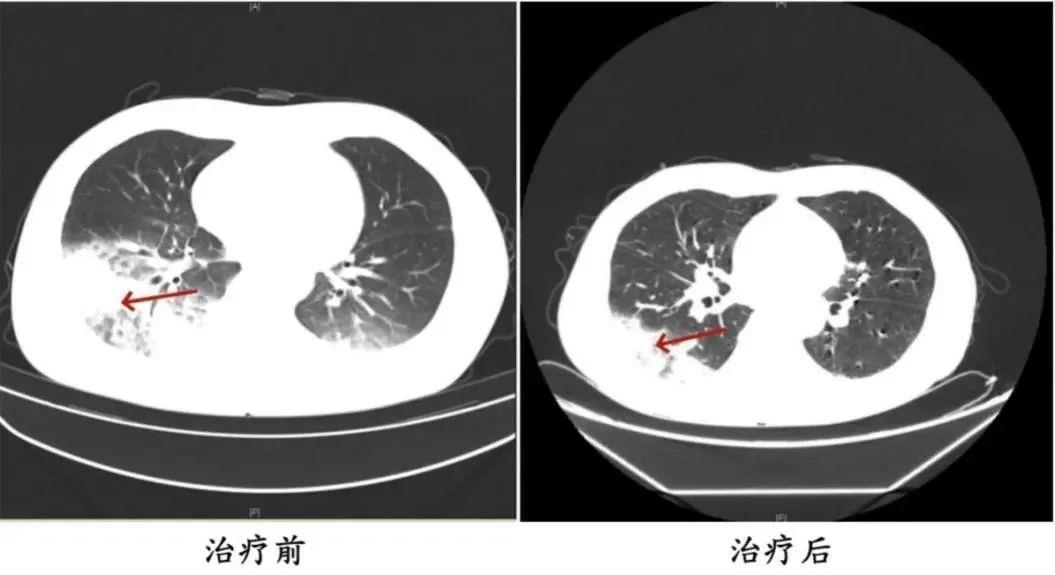

△周先生治疗前后肺部CT影像

根据医生描述,李先生吹了3天冷气后开始出现肌肉酸痛、头痛、发热和咳嗽等症状。起初,他以为只是感冒,但吃了感冒药都不见效,反而愈发严重。入院之后,胸部CT显示李先生的左肺已出现大面积白色影像,几乎占据肺部一半。经过检测,最终确认是嗜肺军团菌肺炎。

不仅是家用常规空调,久未清洗的车载空调也可能成为病菌的“温床”。2024年6月,湖南的周先生驾车出差时,因为天气热,启动了久未清洗的车载空调,每天在车上的时间超过十个小时,回来后就出现了和李先生类似的症状。经过检查,同样确诊为军团菌肺炎。